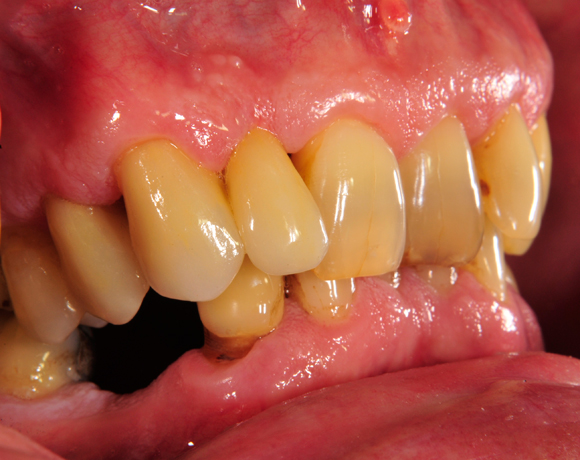

Vollkeramische Implantatkronen aus e.max lassen sich jederzeit mit vollkeramischen Kronen auf natürlichen Zähnen kombinieren ohne, dass ein Unterschied zu natürlichen Zähnen erkennbar ist.

Bei diesem Patienten wurde der nichterhaltungswürdige Zahn 12 mit einem Zerameximplantat versorgt. Nach der Einheilphase wurden auch die Zähne 14 und 13 mit e.max Kronen versorgt